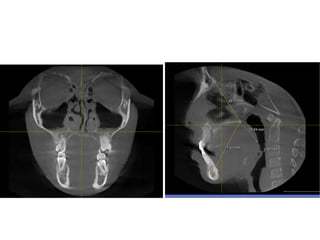

RME

• Maxillary constriction in particular has been

postulated to play a role in the pathophysiology

of OSA because of its association with low tongue

posture that may contribute to the orophayrnx

airway narrowing (Subtelny 1954).

• Pirelli et al. grouped 31 children with OSA and

followed them up to 4 months after RME

treatment. All of these children had their apnea-

hypoapnea index decreased while their mean

maxillary cross sectional width expanded to

about 4.5mm.